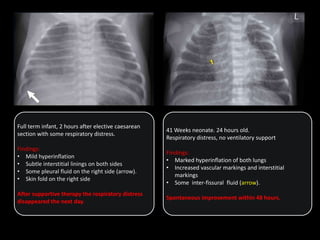

Full term infant, 2 hours after elective caesarean

section with some respiratory distress.

Findings:

• Mild hyperinflation

• Subtle interstitial linings on both sides

• Some pleural fluid on the right side (arrow).

• Skin fold on the right side

After supportive therapy the respiratory distress

disappeared the next day.

41 Weeks neonate. 24 hours old.

Respiratory distress, no ventilatory support

• Marked hyperinflation of both lungs

• Increased vascular markings and interstitial

markings

• Some inter-fissural fluid (arrow).

Spontaneous improvement within 48 hours.